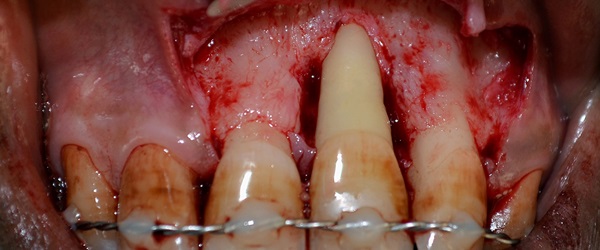

Periodontic Treatment (Gums)

Oral & Maxillofacial Surgery